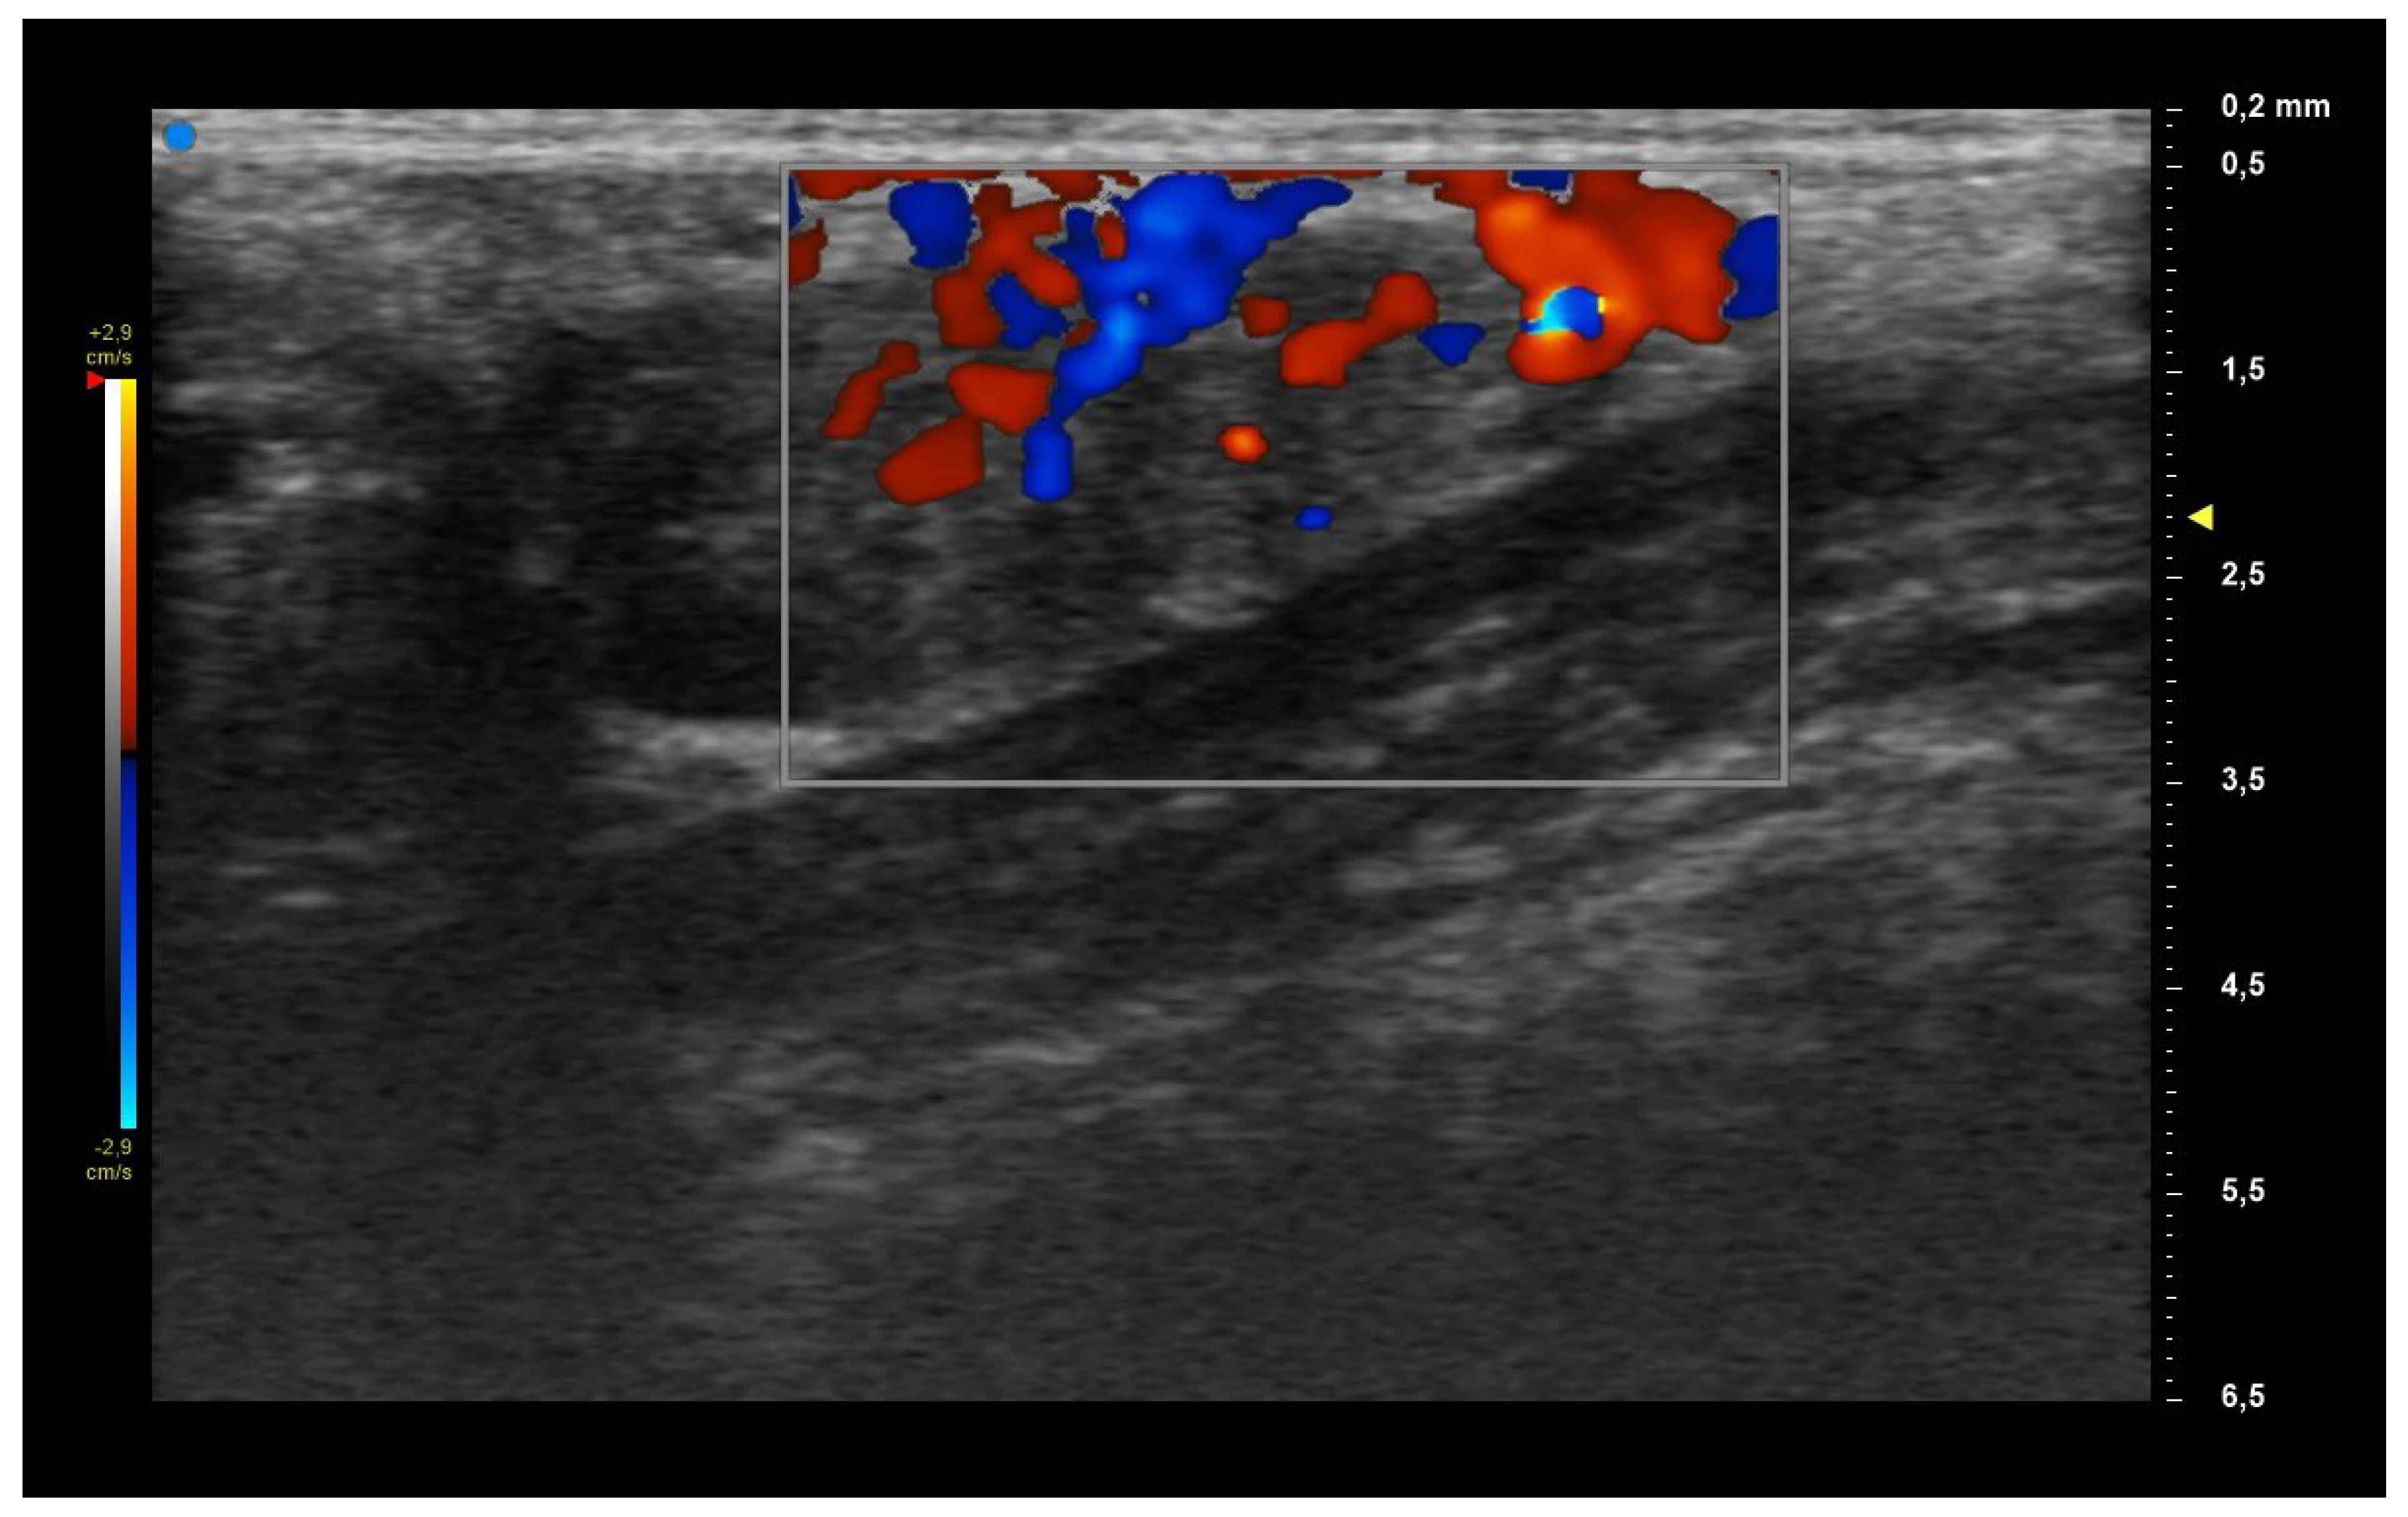

| UHFUS Characteristics | Sicca Syndrome (n = 4) | Parotitis (n = 2) | Non-Sicca, Non- Parotitis (n = 6) | Total (n = 12) |

|---|---|---|---|---|

| Grade 1 | 3 (75%) | 1 (50%) | 4 (67%) | 8 (67%) |

| Grade 2 | 0 (0%) | 1 (50%) | 1 (17%) | 2 (17%) |

| Grade 3 | 1 (25%) | 0 (0%) | 1 (17%) | 2 (17%) |

| Mild vascularization | 1 (25%) | 1 (50%) | 1 (17%) | 3 (25%) |

| Moderate vascularization | 3 (75%) | 1 (50%) | 5 (83%) | 9 (75%) |